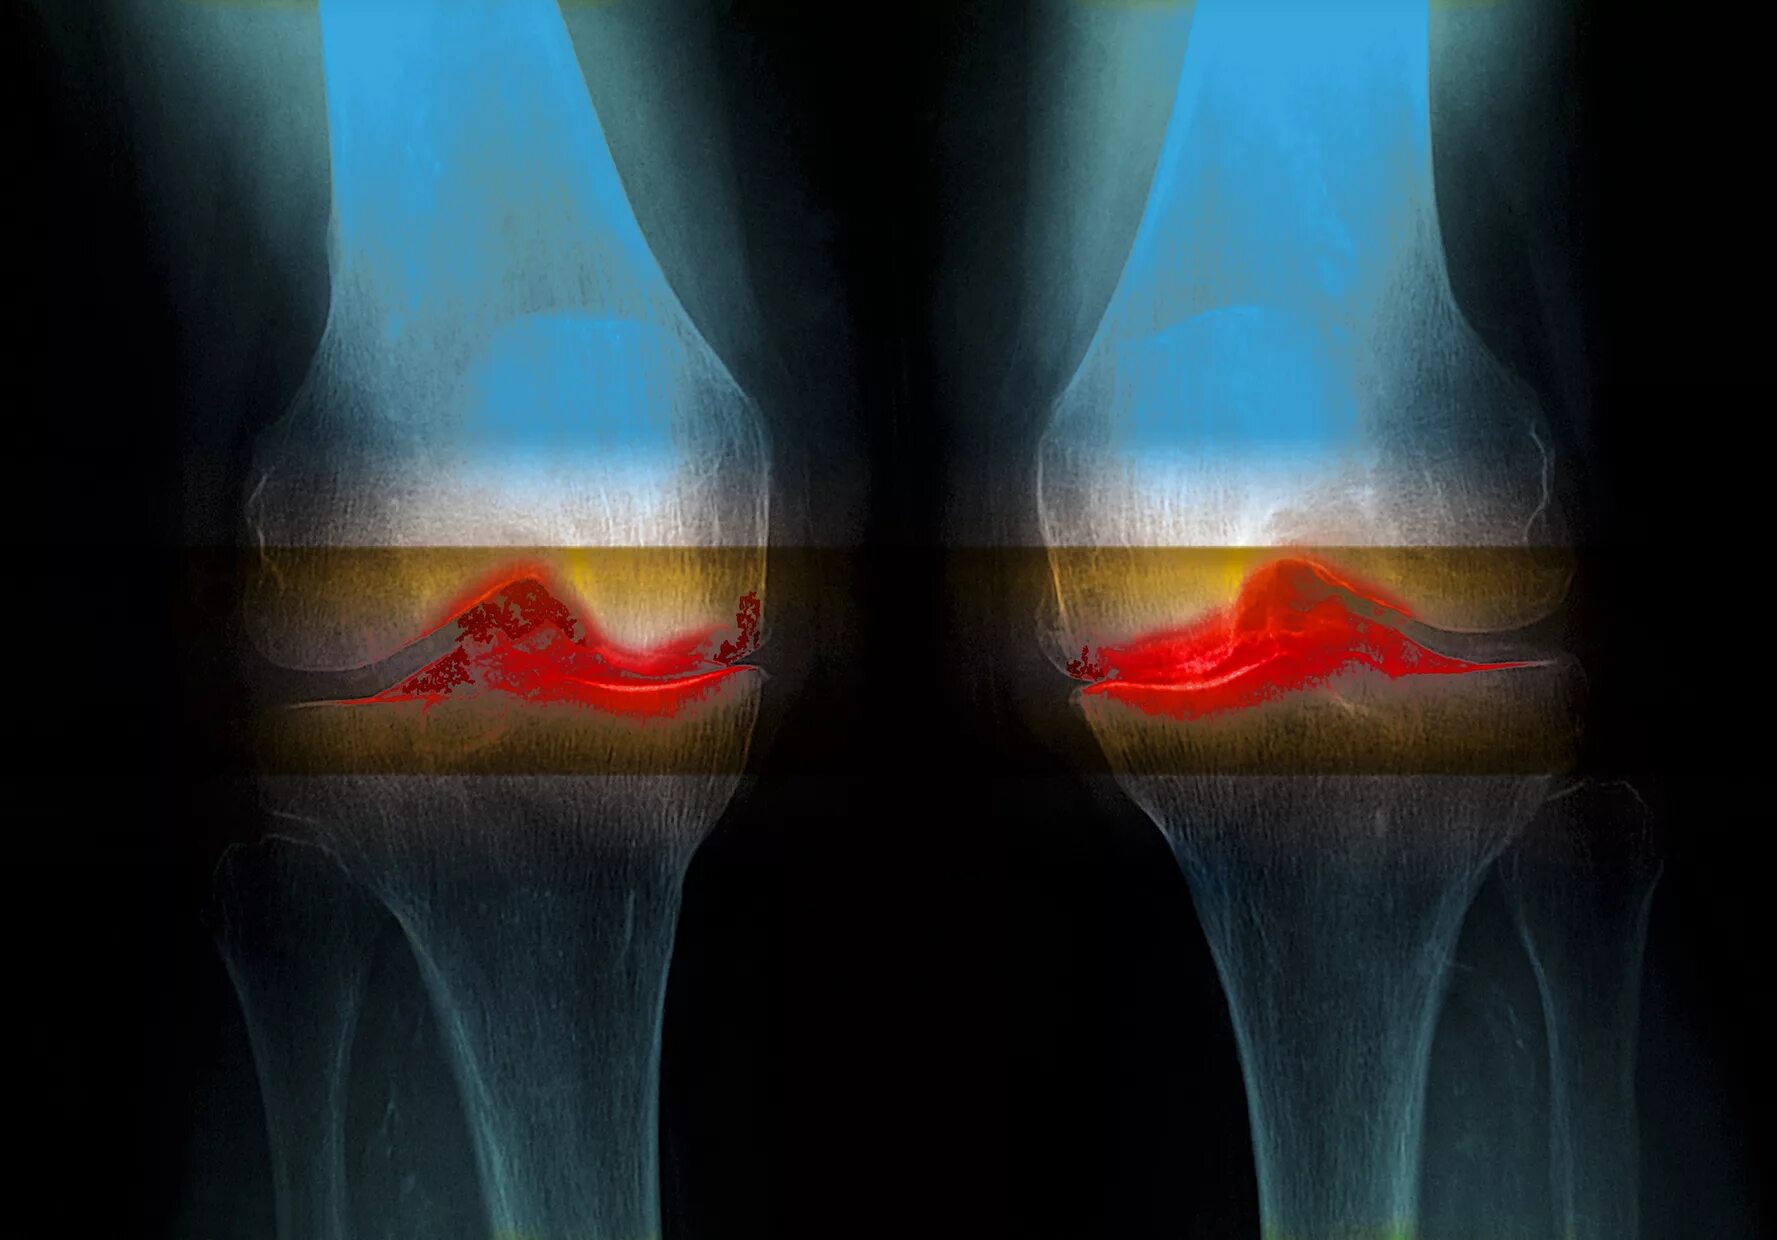

Явления остеоартроза